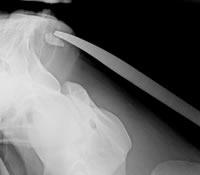

- C Bogen Operationen

- Osteosynthese